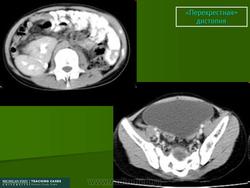

Перекрестная дистопия почки

Перекресная дистопия почки встречается редко и характеризуется перемещением одной из почек за срединную линию тела. Таким образом, обе почки оказываются по одну сторону позвоночника. Очень часто обе почки срастаются в один орган, но при этом имеют каждая собственные сосуды и мочеточники. Обычно такая аномалия не проявляется клинически и ее диагностируют при помощи ультразвукового исследования и экскреторной урографии. Оперативное лечение проводят только если возникает заболевание, требующее оперативного вмешательства (гидронефроз, опухоль, мочекаменная болезнь, пиелонефрит).